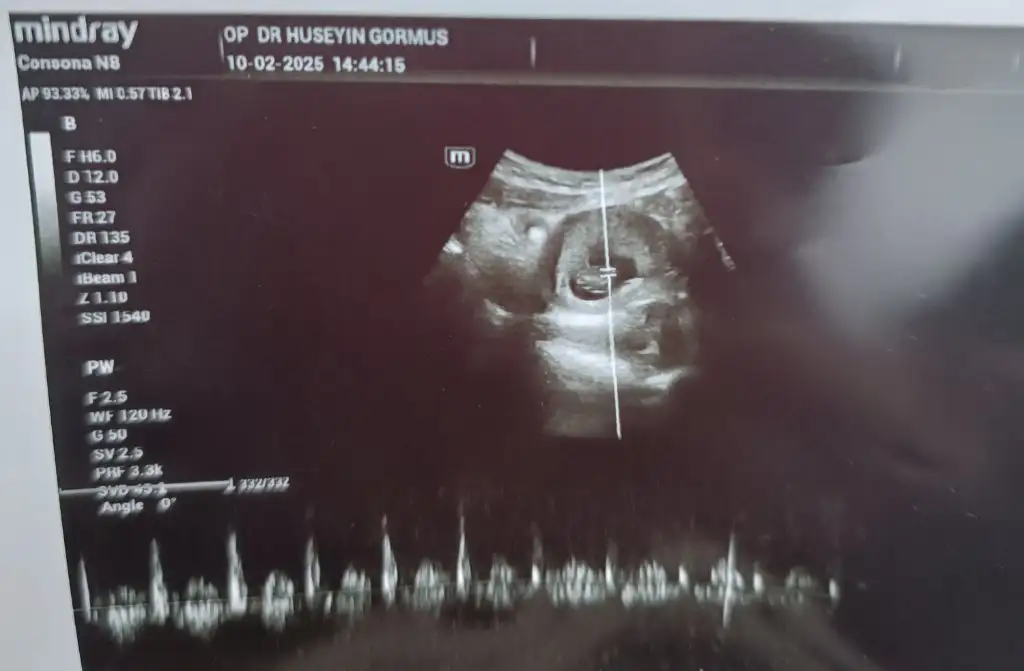

lütfen bana da yorum yapar mısınız fotografı paylastım simdiden tesekkür ederim